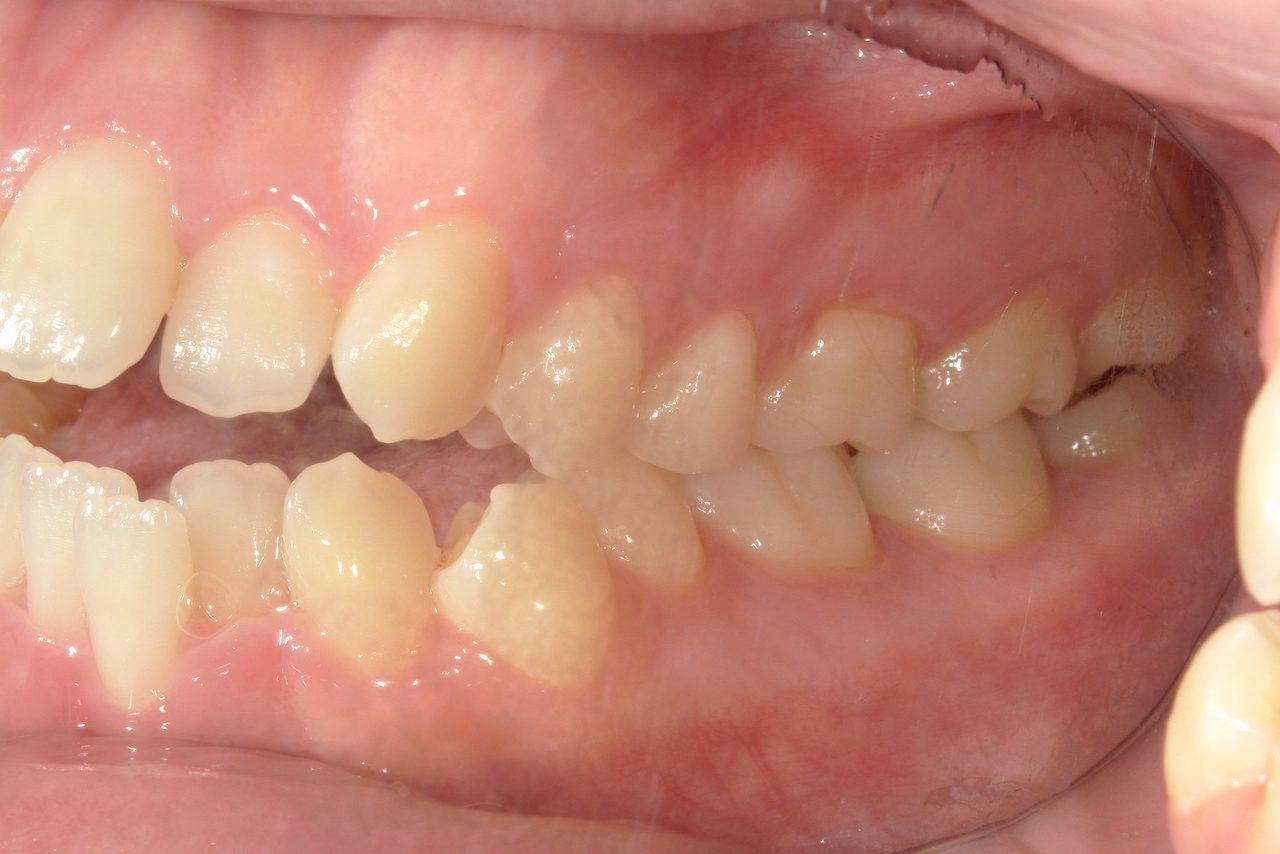

Before

浜松市中央区・自動車学校前駅のインビザラインの症例

R.K. 40代女性

下の歯が上の歯よりも出ているのが気になる、との主訴で来院。下顎前歯を内側に入れることで、下顎前突と叢生を治しました。

治療の期間:R5. 4/18〜R6. 10/23

治療の価格:66万円